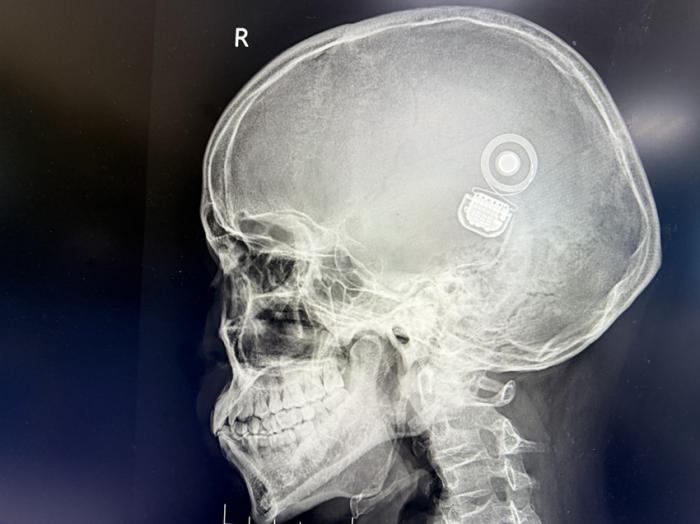

“成人耳蜗植入对电极精准度要求极高,尤其是长期听力剥夺导致的神经退化,需个性化制定手术方案。”湘南学院附属医院耳鼻咽喉头颈外科主任邓忠教授介绍,团队采用高分辨率影像导航技术,将24通道电极精准植入曹先生耳蜗鼓阶,术中神经反应测试显示信号传导良好。

术后一周,曹先生耳部切口愈合良好,电极阻抗测试结果稳定。据悉,他将于4月中旬接受人工耳蜗首次开机调试。“工程师会根据神经反应阈值,为他‘定制’声音感知参数。”邓忠教授解释。